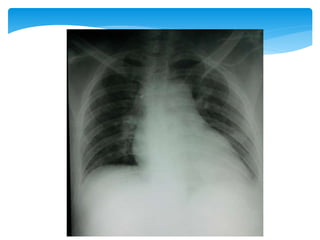

 TC de tórax: (11/07/12):

 lesão escavada, com limites parcialmente definidos

apresentando broncogramas de permeio no segmento

superior do lobo inferior esquerdo (dimensões: 5.3 x 3.4 cm).

 Massa na pirâmide basal anterior do lobo inferior esquerdo

apresentando atenuação heterogênea como imagens

hipoatenuantes em permeio que podem traduzir necrose/

cistificação.

 Pequeno nódulo com baixa atenuação no segmento superior

do lobo inferior direito medindo aproximadamente 1 cm de

diâmetro.